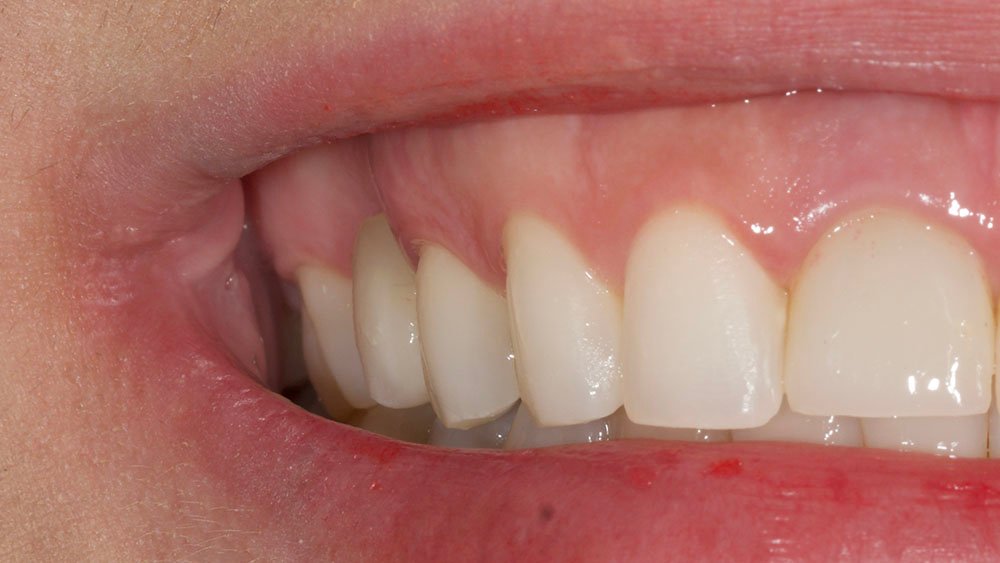

Para este relato de caso clínico selecionou-se a paciente A. S. P, do gênero feminino, de 22 anos, que procurou a Clínica de Especialização em Implantodontia devido a uma perda dentária do elemento 15 por trauma, culminando como queixa principal a ausência do elemento dental e a gengiva aprofundada.

Durante a anamnese, a paciente apresentou um bom estado de saúde geral e não relatou nenhum dado médico relevante que impossibilitasse o tratamento. No exame físico intraoral, observou uma boa condição de saúde bucal, notando-se apenas a ausência do elemento 15 com uma depressão óssea no vestibular. Dessa forma, objetivou-se um plano de tratamento baseado na utilização da técnica de rolo modificada e colocação de dente provisório.